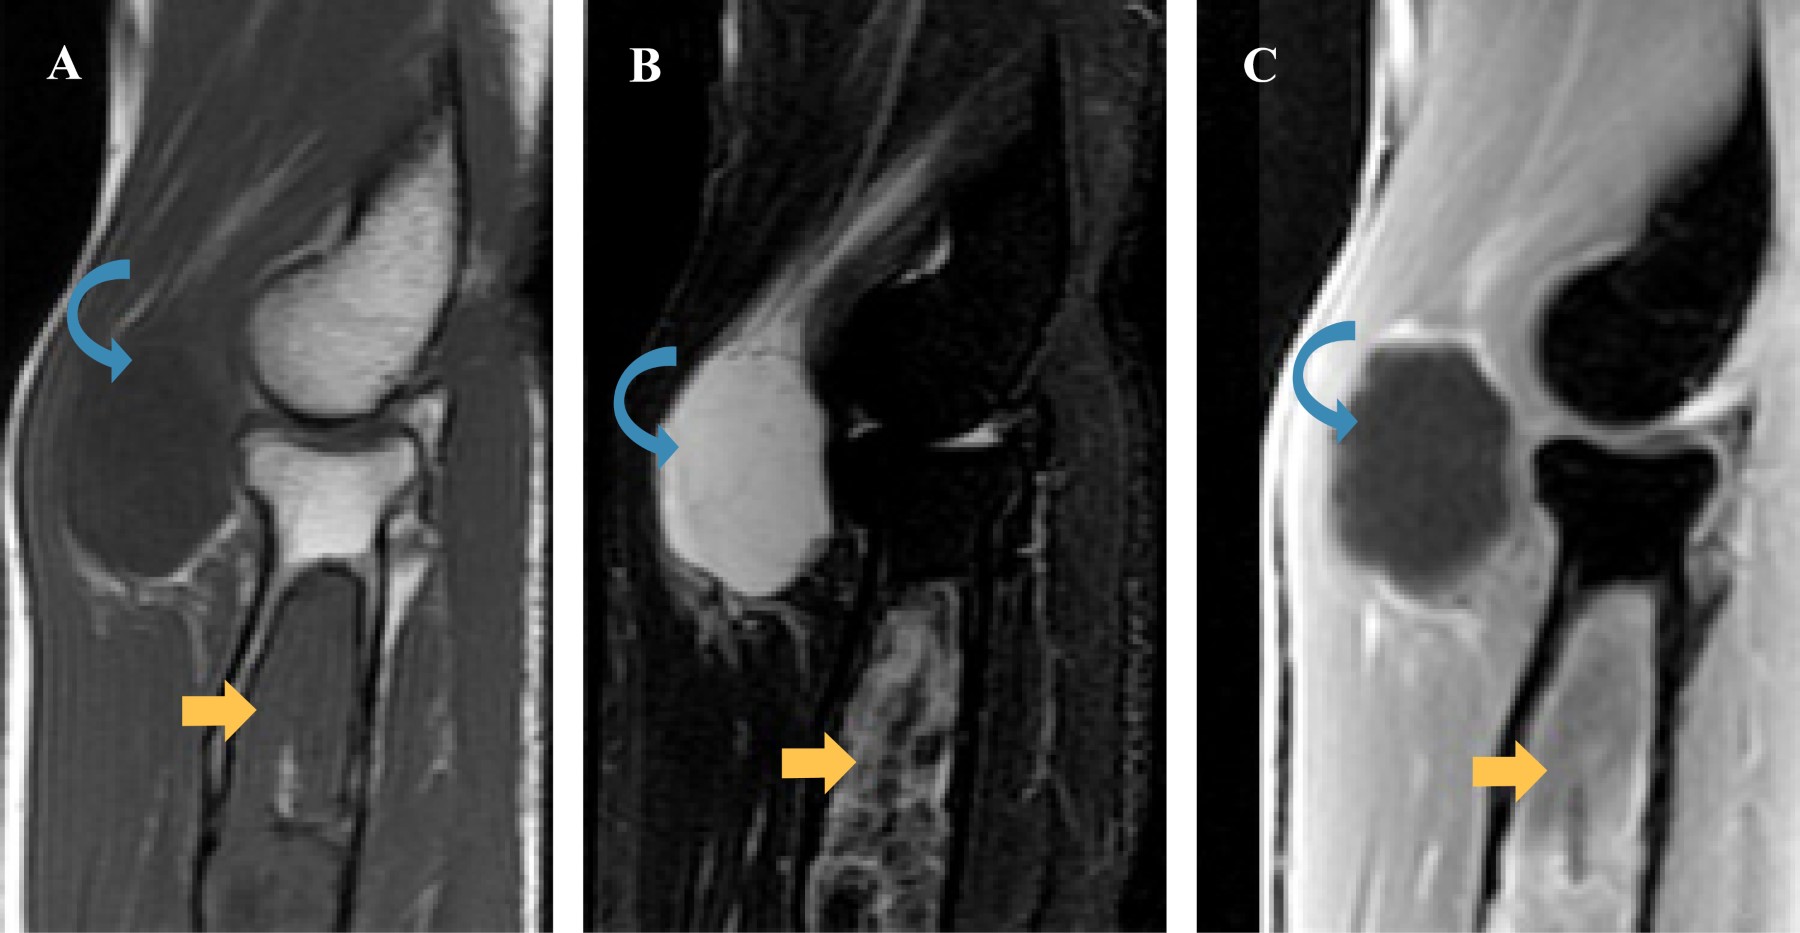

Como parte del abordaje diagnóstico, solicitamos tomografía computada simple y resonancia magnética nuclear simple y contrastada. Por su relevancia, incluimos a continuación las imágenes obtenidas por resonancia magnética nuclear.

Se observa una lesión ovoidea, bien delimitada, localizada en la región anterior del codo, entre el músculo braquiorradial y los tendones del braquialis y bíceps, homogénea con respecto a los músculos en T1, hiperintensa en STIR y sin realce tras la administración del medio de contraste (flecha curveada) en relación con mixoma. Asimismo, se observa otra lesión en la región metafisiodiafisaria proximal del radio, la cual es de localización central, zona de transición estrecha con bordes esclerosos, heterogénea de predominio isointenso con respecto al músculo en T1, heterogénea predominantemente hiperintensa en STIR, con realce heterogéneo tras la administración de medio de contraste (flecha) compatible con displasia fibrosa (Figura 1).

Figura 1